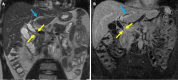

Endoscopic retrograde cholangiopancreatography (ERCP) is a cornerstone procedure for the diagnosis and management of pancreatic and hepatobiliary diseases. Although its diagnostic role has been increasingly supplanted by noninvasive imaging modalities such as magnetic resonance imaging (MRI) and magnetic resonance cholangiopancreatography, the therapeutic applications of ERCP have continued to expand. ERCP is widely used and has a generally favorable safety profile. However, it is important to recognize expected post-procedural imaging findings and serious complications that can arise. The increasing complexity of therapeutic interventions and the growing volume of procedures have led to a higher incidence of complications that often present with overlapping clinical and laboratory features, underscoring the critical role of imaging in differential diagnosis. This review focused on the typical normal ERCP findings and the imaging characteristics of common complications, including pancreatitis, bleeding, ERCP-related infections, perforations, and stent-related complications. Computed tomography (CT) is particularly valuable in timely recognition, management, and surgical decision-making for these complications. Furthermore, MRI offers a radiation-free alternative for managing complications in selected patients. Therefore, radiological modalities, particularly CT and MRI, are critical tools for the rapid diagnosis, management, and surgical decision-making processes for post-ERCP complications.